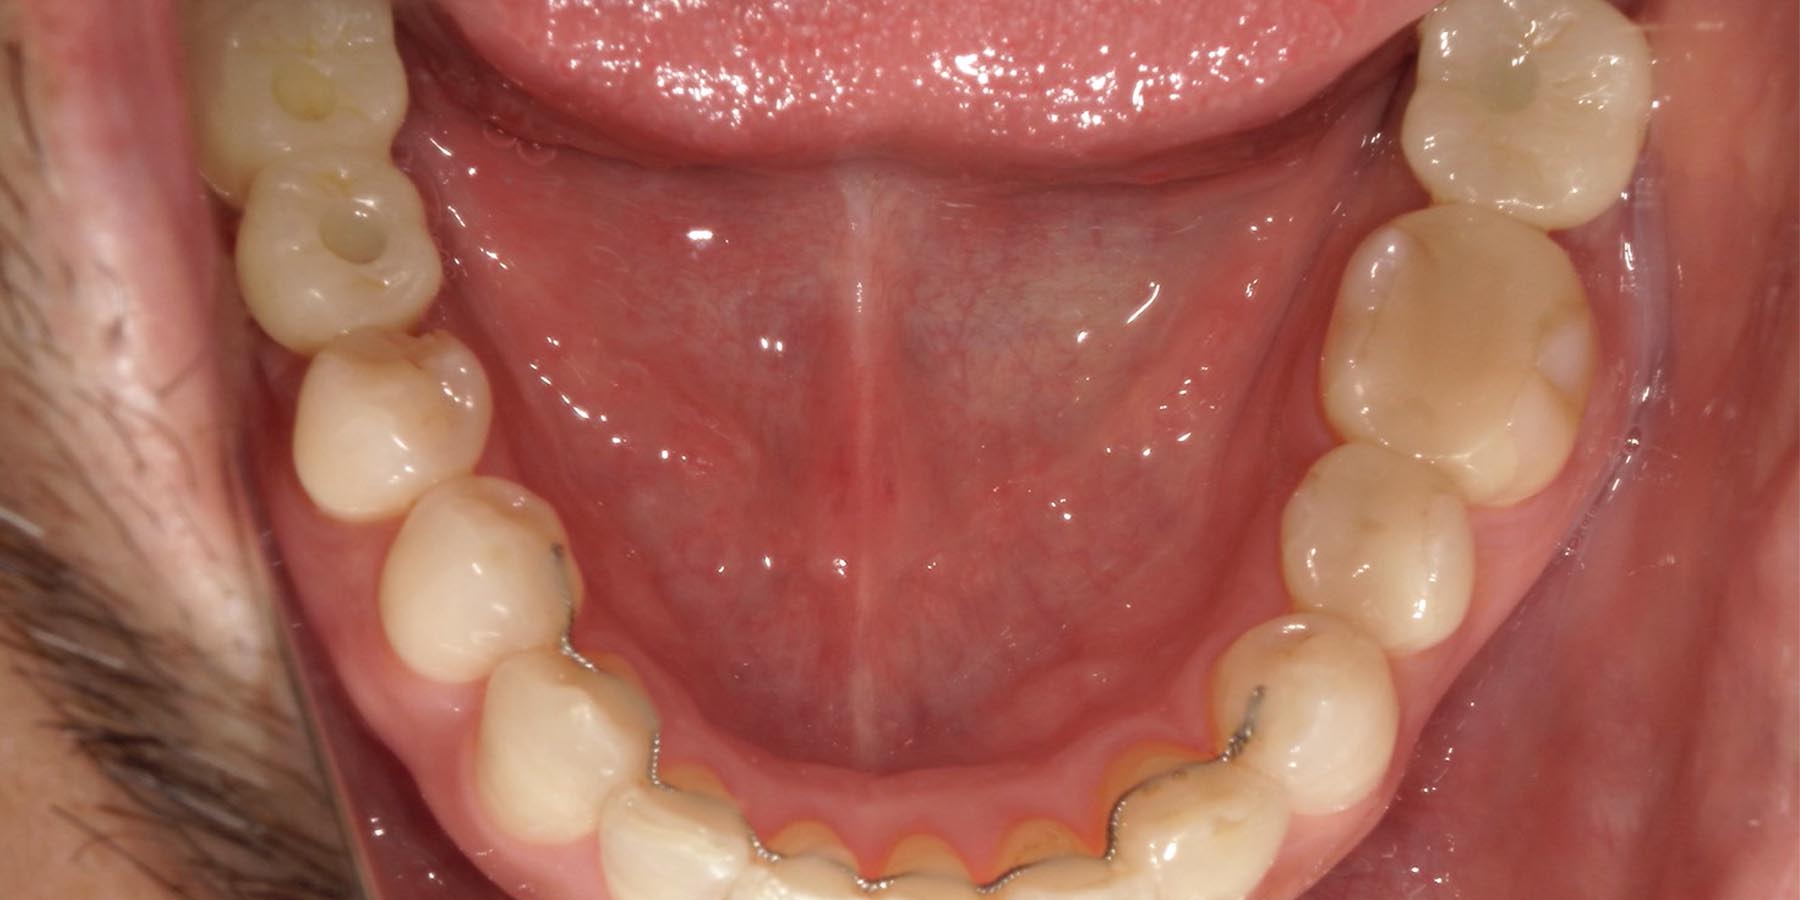

治療前